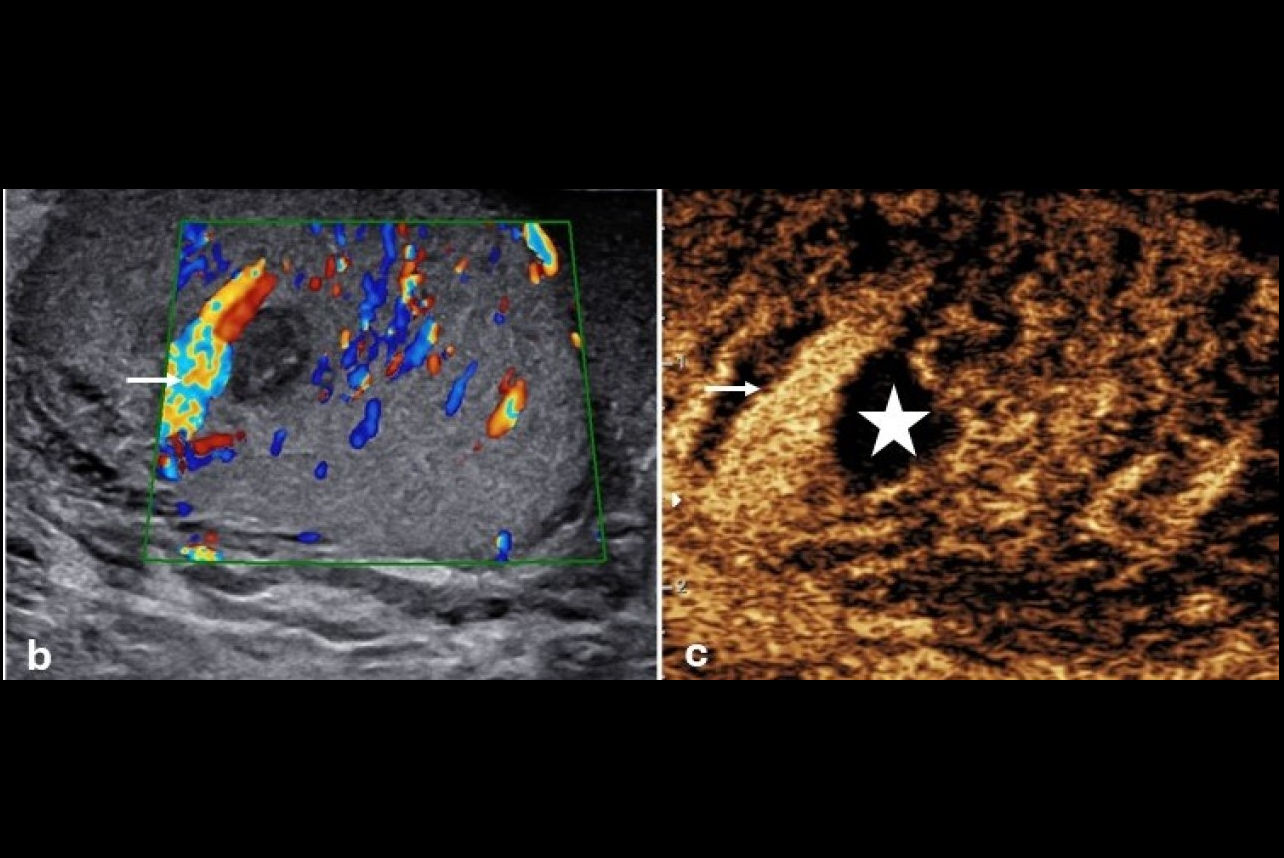

Contrast-enhanced ultrasound excels in scrotal imaging